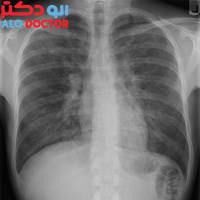

رییس انجمن آسم و آلرژی ایران با اشاره به اهمیت توجه به بیماری های مزمن تنفسی گفت: سالانه 4.6 میلیون نفر در جهان در اثر ابتلا به این بیماری ها جان خود را از دست می دهند.

یک فوق تخصص ریه با اشاره به اهمیت تغذیه در بیماری‌های ریوی، گفت: نوع تغذیه و حتی شرایط روحی و روانی فرد بر کنترل یا تشدید بیماری‌های ریوی بسیار موثر است.

آخرین وضعیت بیماری‌های مزمن تنفسی و آسم در ایران و دنیا و همچنین هزینه‌های درمان این بیماران از جمله مباحثی بود که در نشست خبری روز جهانی آسم مورد بحث و بررسی قرار گ